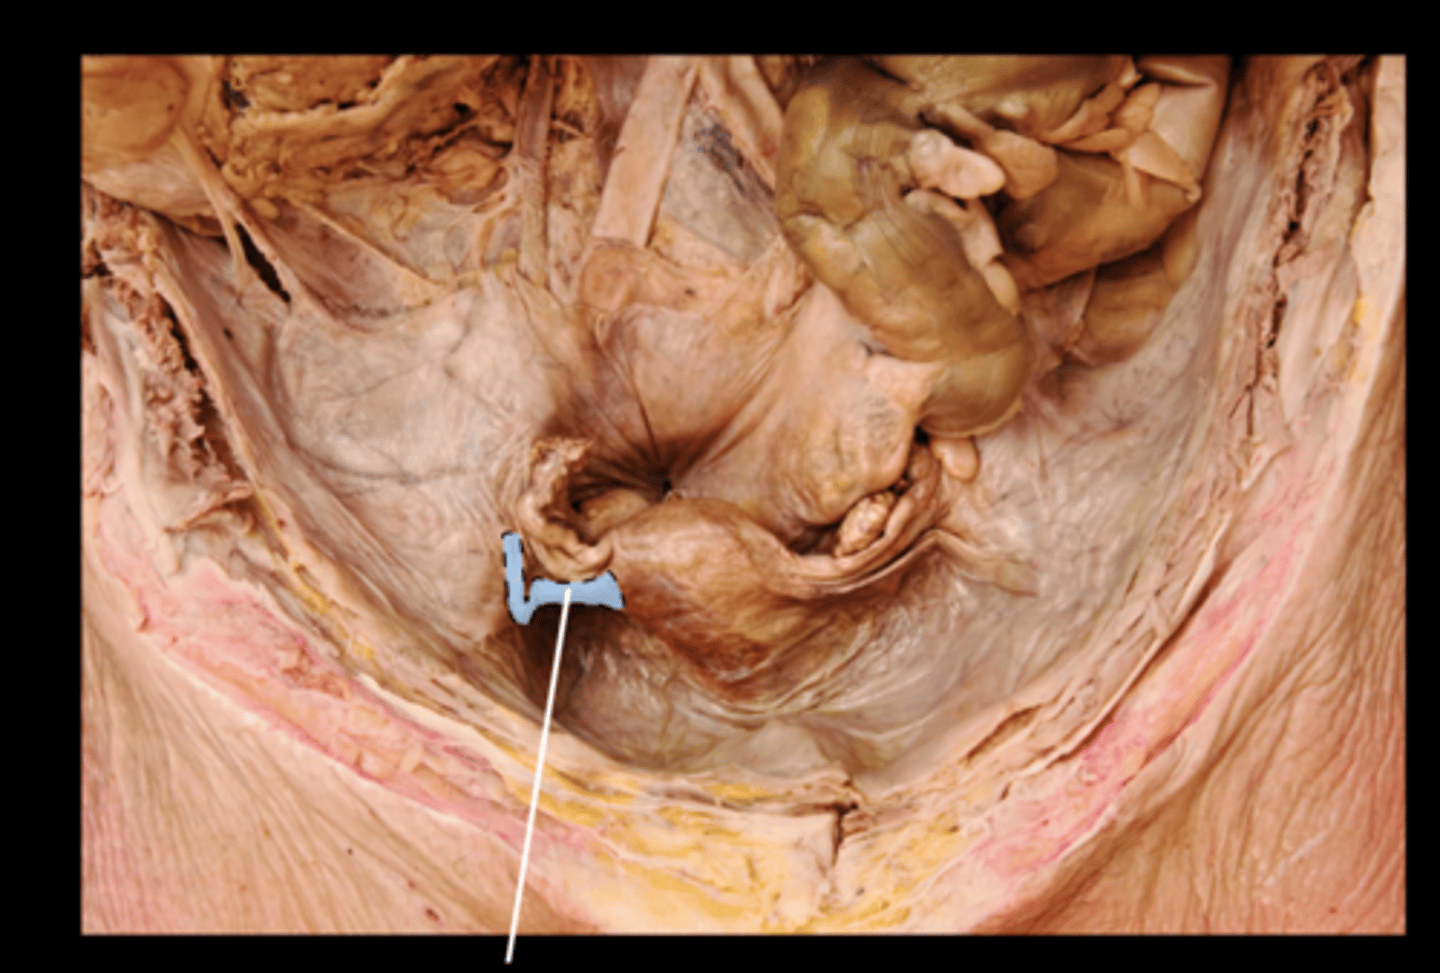

Ileocecal Valve

Internal Anal Sphincter

External Anal Sphincter